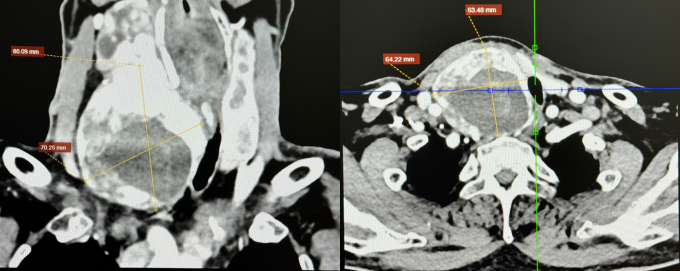

Ông Kỳ, 67 tuổi, có tiền sử tăng huyết áp, rối loạn lipid máu, suy thận mạn giai đoạn 3. ThS.BS.CKI Phạm Ngọc Minh Thủy, khoa Ngoại Tim mạch, Trung tâm Tim mạch, Bệnh viện Đa khoa Tâm Anh TP HCM, cho biết thùy phải tuyến giáp của ông Kỳ kích thước 68x68x121 mm. Bướu giáp thòng xuống hõm ức, đẩy khí quản, thực quản sang trái, khiến lòng khí quản còn 9 mm (trong khi đường kính bình thường khoảng 20 mm).

Theo ThS.BS Trần Thúc Khang, Phó khoa Ngoại Tim mạch, Trung tâm Tim mạch, đường thở hẹp hơn 55% cho thấy mức độ chèn ép nặng, thực quản nằm sát ngay sau khí quản bị đẩy lệch làm cản trở thức ăn lưu thông xuống dạ dày. Người bệnh có nguy cơ bị khàn tiếng mạn tính, khó thở cấp tính, nhuyễn sụn khí quản (vòng sụn khí quản yếu đi, mất khả năng đàn hồi), ngưng thở khi ngủ, sặc thức ăn vào đường thở... nếu không điều trị kịp thời.